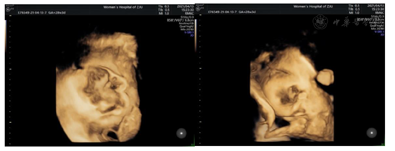

辅助检查:1.本院产前诊断超声检查示:胎位:ROA胎心:147次/分胎动:可及双顶径9.2 cm,头围32.5 cm,股骨长7.2 cm,腹围34.3 cm,胎盘:前壁GrII级,羊水指数:9.0 cm,脐动脉S/D比值2.5。备注:胎儿右侧颜面部见5.2 cm×3.9 cm×3.7 cm不均低回声,局部边界不清,内见丰富血流信号,RI:0.59;右侧上颌骨回声不规则、见回声中断,低回声与该侧上颌骨关系密切;右侧上牙槽处回声不规则、见回声中断;颈部见"U"形切迹(图1,图2,图3,图4)。诊断结果:宫内孕,单活胎,胎儿右侧颜面部不均低回声(肿瘤考虑,恶性可能),目前胎儿脐带绕颈1周。